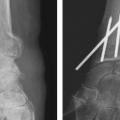

Enfin, il est important d’analyser le versant ulnaire pour savoir si la fracture de l’extrémité inférieure du radius est isolée ou bien associée à une fracture de l’extrémité distale de l’ulna ou encore à une fracture de la styloïde ulnaire. Cette fracture est l’équivalent d’un arrachement du ligament triangulaire du carpe et peut être source d’instabilité radio-ulnaire distale (fig. 10). Il faut également analyser le rapport entre l’épiphyse radiale et l’épiphyse ulnaire, à la recherche d’une inversion de l’index radio-ulnaire témoin d’une ascension de l’épiphyse radiale.

Enfin, le fixateur externe ne doit pas être utilisé seul car une traction excessive est un facteur de risque d’algo­neurodystrophie. Il doit être ajouté comme moyen de protection d’une ostéosynthèse par broche ou plaque précaire. Son rôle est de neutraliser les contraintes en compression sur l’extrémité inférieure du radius en cours de consolidation (fig. 14).